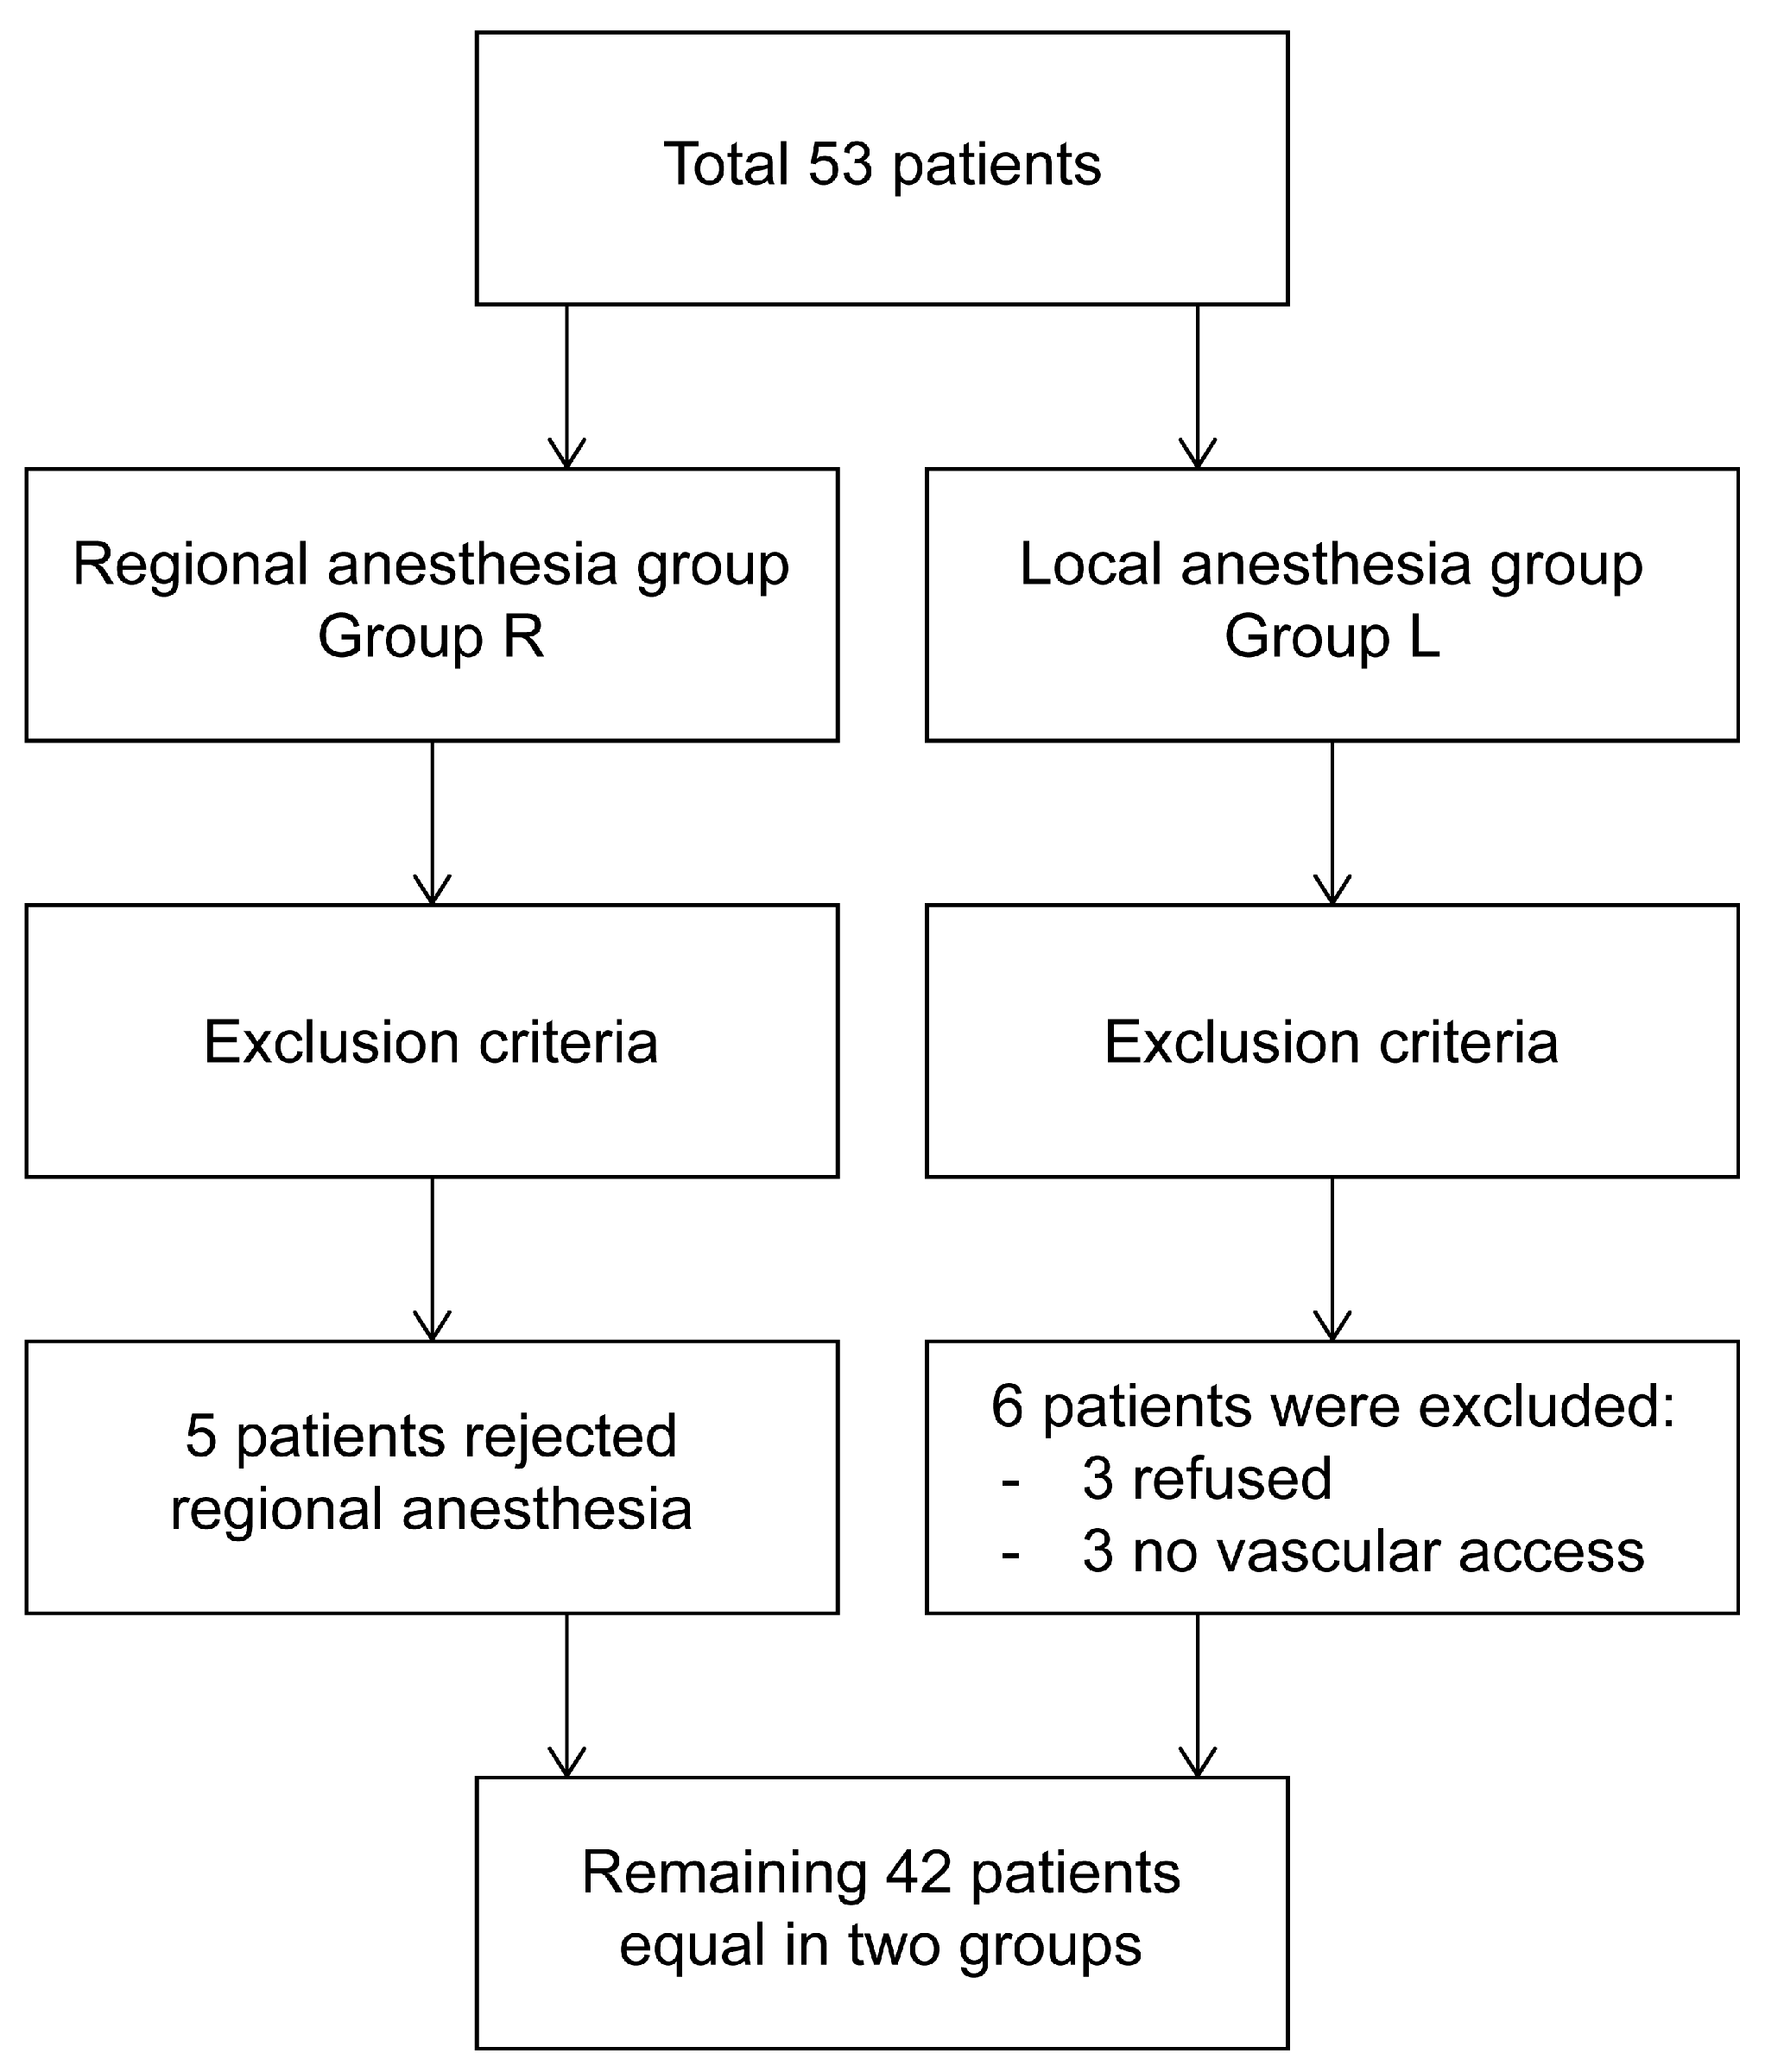

2.1. Patient Selection and Study Design

2.2. Randomization and Blinding